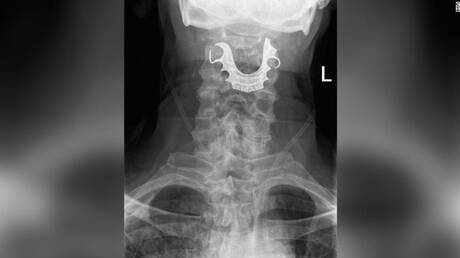

Μία… μασέλα κολλημένη στον λαιμό του είχε επί οκτώ ημέρες ένας 72χρονος, μετά από χειρουργική επέμβαση.